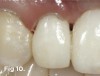

A 38-year-old Caucasian female patient presented with a high smile line and loss of the papilla between tooth No. 7 and edentulous adjacent site No. 8 (Figure 1). Understandably, the patient was unhappy and embarrassed about her esthetic condition. Her dental history revealed tooth replacement of No. 8 with an implant that eventually failed. The site had been previously bone grafted upon implant removal. She was given a composite pontic No. 8 bonded to a tooth No. 7 composite veneer as a transitional restoration. The implant was positioned too close to the proximal surface of tooth No. 7, which stripped the periodontal attachment of the root and ultimately caused loss of the papilla (Figure 2). As previously outlined, the treatment sequence would be to first provide a provisional restorative solution to evaluate the projected outcomes and assess if the patient was willing to undergo orthodontic therapy. In this situation, a full-coverage crown No. 7 with a cantilevered pontic No. 8, with artificial acrylic gingiva to replace the lost papilla on the mesial aspect of tooth No. 7 was used as a transitional temporary prosthesis (Figure 3). In addition, a composite resin restoration was placed on the mesial aspect of tooth No. 9 to restore its individual tooth proportion and shape. The patient’s esthetic outcome could now be evaluated with restorative correction alone; it was therefore mutually determined that the correction of her deformity would best be served with additional orthodontic forced eruption therapy. A fixed orthodontic appliance (brackets) was bonded to the teeth and temporary prosthesis. The level of the interproximal pink acrylic was used as a therapeutic guide for the amount of forced eruption required as well as the alignment of the mesial papilla of No. 7 to that of the adjacent papillae height (Figure 4). Floss was used to elevate the amount of vertical movement achieved relative to the adjacent papilla tooth No. 9. Eventually, all the artificial pink acrylic was removed. (Note that the distal papilla on tooth No. 7 also comes more incisal—in fact, it is slightly excessive at the endpoint of treatment [Figure 5]). However, the distal papilla and midfacial tissues of tooth No. 7 can be reshaped through clinical crown lengthening toward the end of treatment prior to definitive restoration, thereby restoring the proper papilla height-to-tooth ratio of 40%. After stabilization of tooth No. 7 for a minimum of 6 months post-orthodontics, an implant was placed in site No. 8. A papilla-sparing incision design was used for flap elevation (Figure 6), bone allograft was used to further augment the facial aspect of the ridge simultaneously with implant placement (Figure 7), and a resorbable membrane was used for guided bone regeneration.

Fig 1. Preoperative extraoral view of patient with significant loss of the papilla on the mesial aspect of tooth No. 7 and a high smile line.

Figure 1